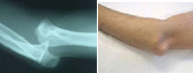

Fracturas de olécranon

El olécranon es la parte superior del cúbito que articula con el húmero para que podamos realizar la flexión y extensión de nuestro codo. Una fractura de olécranon supone la imposibilidad para la realización de esta función. Ocurren tanto en el paciente de edad avanzada como en el joven y suele ser por caídas con el codo en flexión. Dada su relevancia en el movimiento del brazo su reparación debe ser rápida y precisa para evitar secuelas en la bisagra del codo. A través de procedimientos mínimamente invasivos se puede conseguir la restitución articular minimizando los riesgos de grandes cirugías e iniciar el movimiento en un breve período de tiempo.